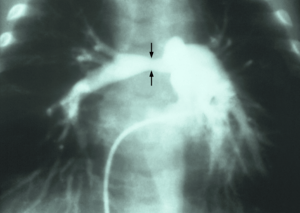

Stenosis of pulmonary artery

| Stenosis of the right pulmonary artery in a patient which was due to a case of congenital rubella. | |

Stenosis of the pulmonary artery is a condition where the pulmonary artery is subject to an abnormal constriction (or stenosis).[1] Peripheral pulmonary artery stenosis may occur as an isolated event or in association with Alagille syndrome, Berardinelli-Seip congenital lipodystrophy type 1, Costello syndrome, Keutel syndrome, nasodigitoacoustic syndrome (Keipert syndrome), Noonan syndrome or Williams syndrome.

It should not be confused with a pulmonary valve stenosis, which is in the heart, but can have similar hemodynamic effects. Both stenosis of the pulmonary artery and pulmonary valve stenosis are causes of pulmonic stenosis.